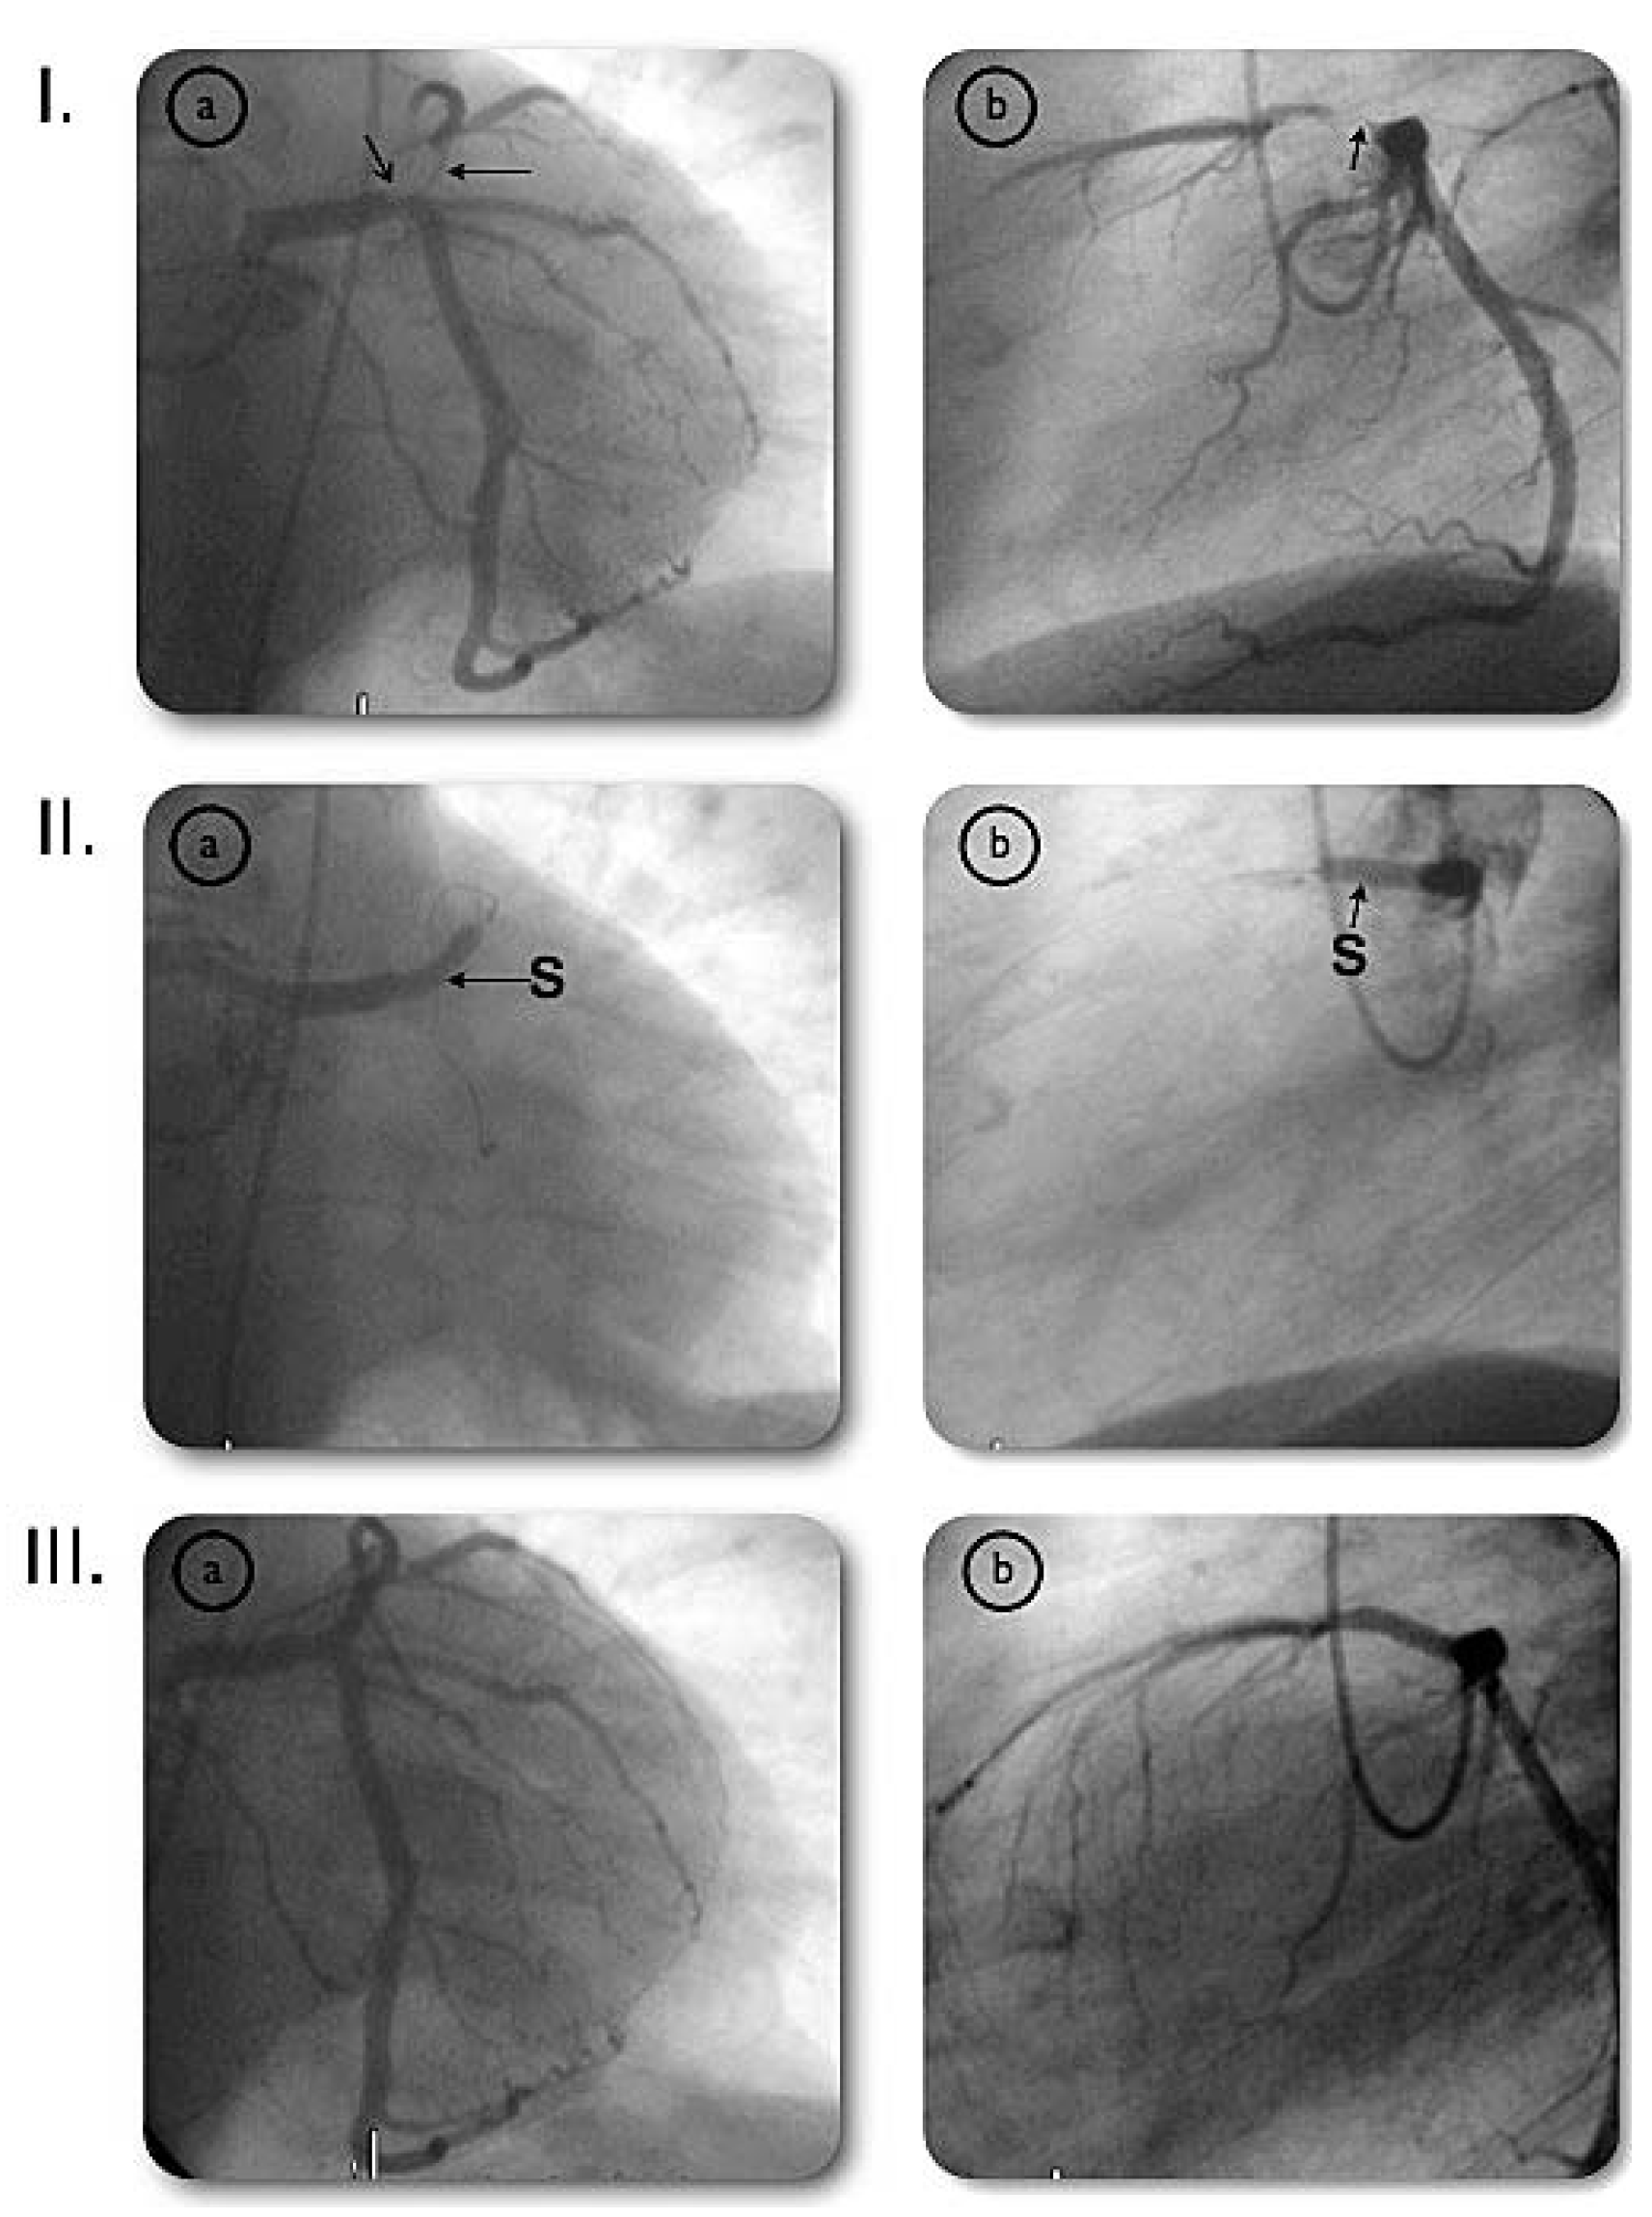

Very Late Stent Thrombosis of a Paclitaxel-Eluting Stent After Left Main Coronary Artery Stenting

Case report